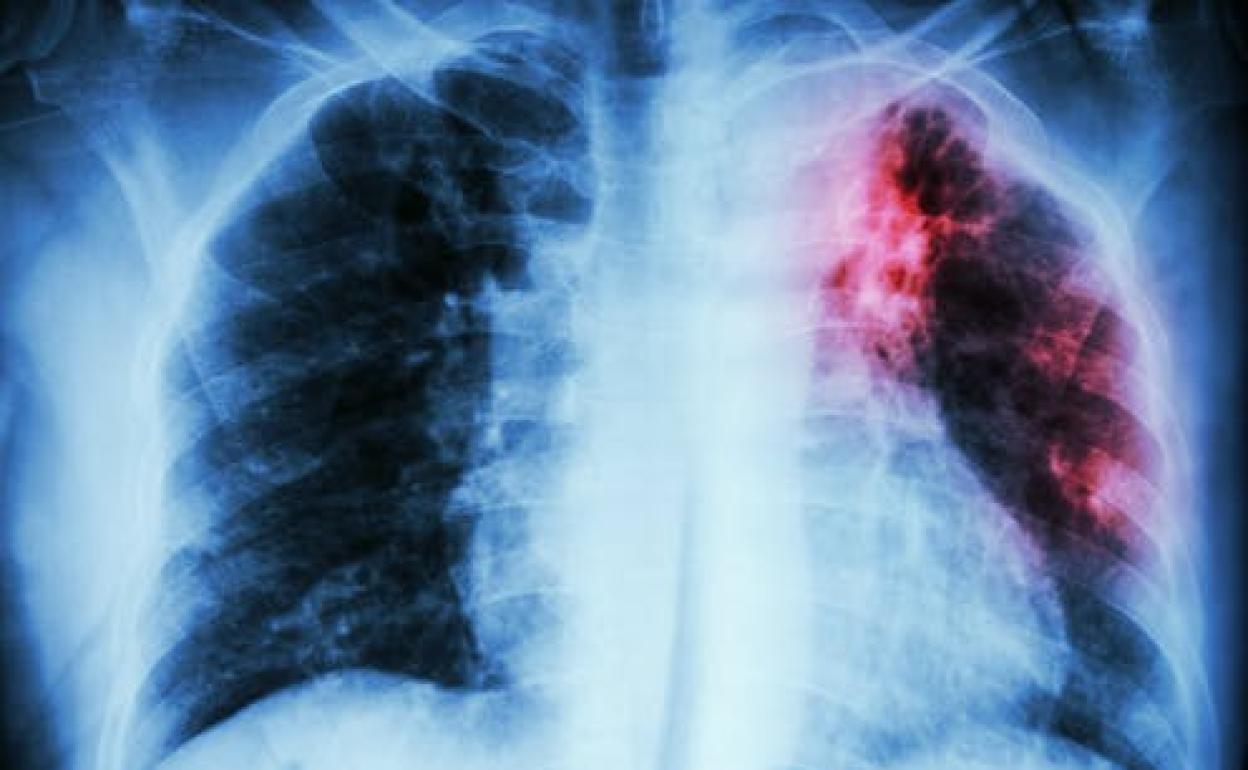

Tuberculosis y covid-19 son enfermedades infecciosas de transmisión aérea. Afectan mayoritariamente al sistema respiratorio y manifiestan una tríada clásica de síntomas: tos, fiebre y disnea. Esto dificulta inicialmente el diagnóstico diferencial, especialmente en países con alta incidencia de tuberculosis.